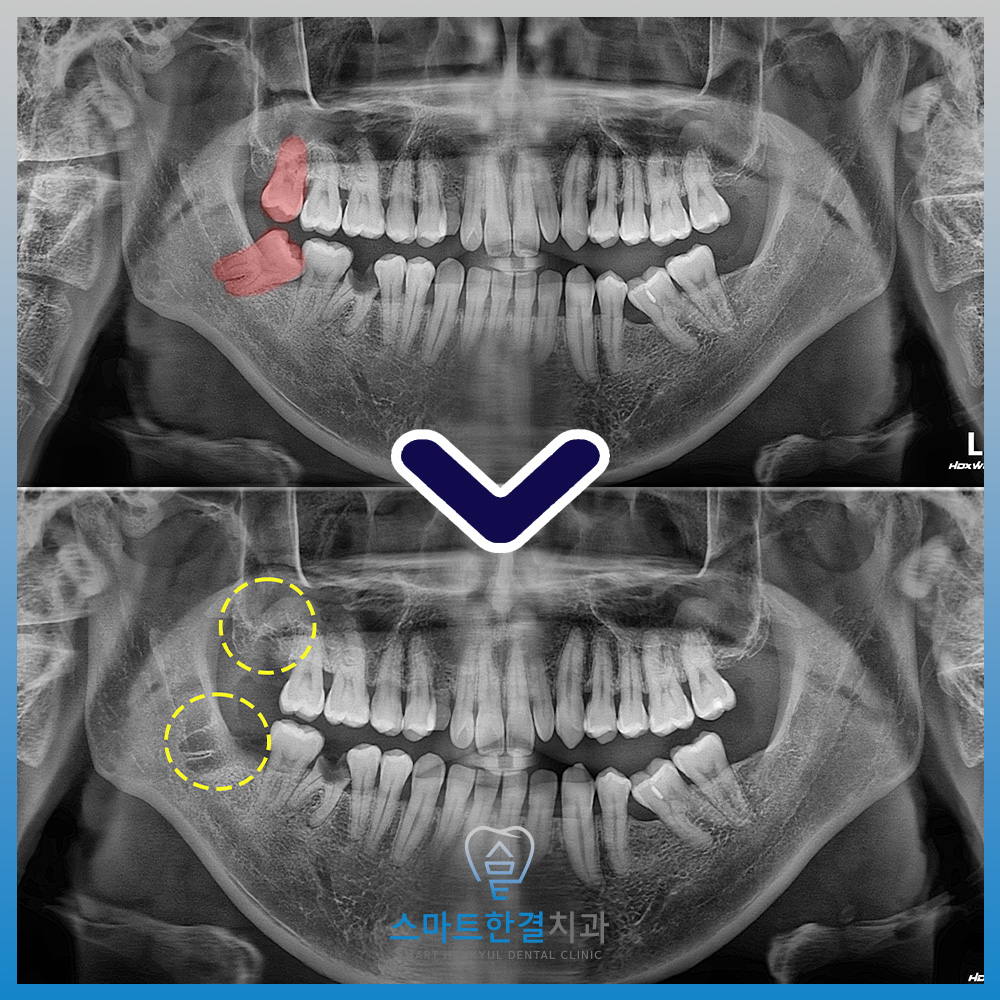

오늘은 오른쪽 위, 아래 사랑니 발치를

진행한 환자분을 소개해 드릴게요.

위쪽 사랑니는 올바르게 자라나있어

불편감이 없었지만

아래 사랑니는 앞 치아 쪽으로

비스듬히 자라나 있어 관리가 안 되어

잇몸이 붓고 그로 인해 앞 치아에

충치가 생길까 걱정되어 내원해 주셨어요.

오른쪽 위, 아래 사랑니 모두

깨끗하게 발치한 모습이에요.

비스듬히 누워 난 사랑니는

잇몸을 약간 절개하여 발치를 하며

필요시에는 치아를 분할하거나

뼈 일부를 삭제하여 발치를 하기 때문에

화서동치과 스마트한결치과

구강악안면전문의의 숙련된 진료가 필요해요.